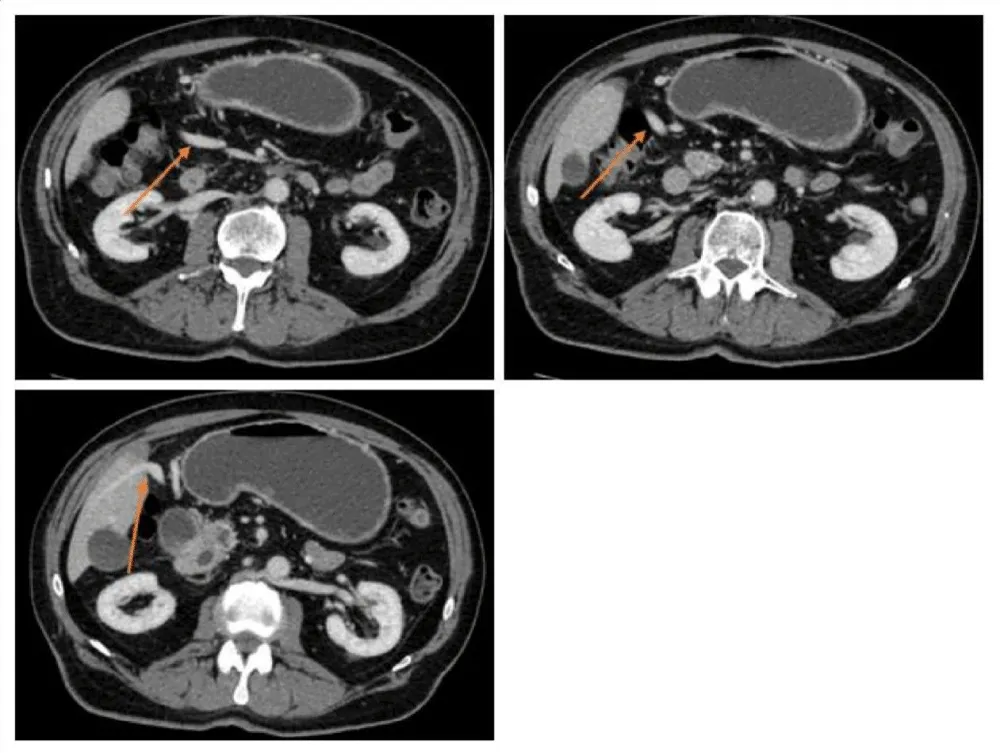

Duplicated portal vein:

1. portal vein in regular position, formed from the inferior mesenteric vein and the splenic vein, supplying segment III, IVb, and V (Figures 1,2).

2. portal vein, which forms from the superior mesenteric vein entering the liver in the ligamentum teres hepatis, supplying the other segments (Figure 3).

3. Both portal veins are connected extrahepatically via a 3 cm anastomotic vein (Figure 4).

Figure 2: CT scan presenting the first portal vein forming from V. mesenterica inferior and V. lienalis.

Figure 3: CT scan presenting a second portal vein forming from V. mesenterica superior, entering the Liver via the ligament. Teres hepatis.

Figure 4: CT scan presenting the extrahepatic interportal anastomotic vein.

Two inferior vena cavae are present:

1. Forming from each iliac vein, dorsally passing the liver as well as the heart, draining into the superior vena cava via the V. azygos

2. A short inferior vena cava, formed from the confluence of the hepatic veins, drains directly into the right atrium